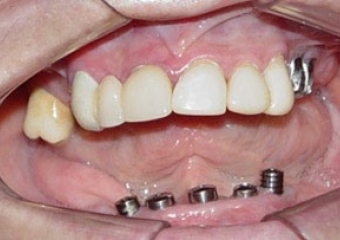

Imagem Implantes Instalados